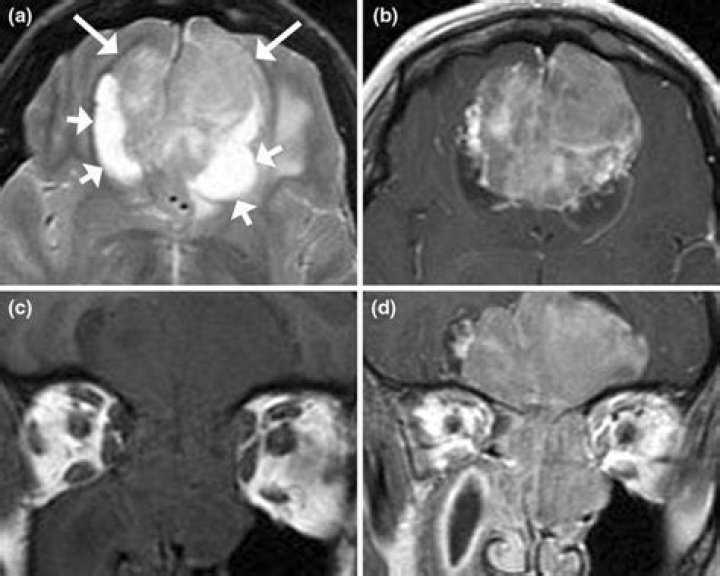

How is olfactory neuroblastoma diagnosed?

Imaging: If you have symptoms of olfactory neuroblastoma, your doctor will use imaging scans such as X-ray, CT, and MRI to look at where the tumor is and how big it is. They will also check for signs that the tumor has spread to other parts of the body.